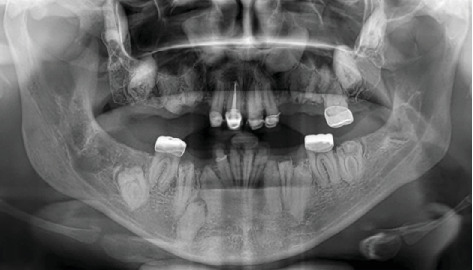

牙发育不良是一种影响牙齿成熟和形成的牙齿异常,导致牙釉质和牙本质发育不全和低钙化。它可以影响一个或几个象限的牙列,虽然广泛的累及是极其罕见的。确切的原因尚不清楚,但创伤、感染、营养或代谢不足被认为是可能的因素。诊断需要结合临床和放射学检查结果。临床上表现为小牙呈黄色或褐色变色,可影响初级和恒牙。放射照相时,放射密度降低,引起模糊或“鬼牙”外观。组织学上,这些牙齿表现为柱状牙釉质,球间牙釉质,以及被称为类牙釉质聚集体的牙釉质样钙化。治疗取决于牙齿受累的程度和患者的年龄。本文报告了一名31岁的女性,她在其普遍形式中表现出这种罕见的异常,使她成为文献中报道的年龄最大的患者。

Odontodysplasia is a dental anomaly that affects the maturation and formation of teeth, resulting in hypoplasia and hypocalcification of both enamel and dentin. It can affect one or several quadrants of the dentition, although generalized involvement is extremely rare. The exact cause is unclear, but trauma, infection, and nutritional or metabolic deficiencies have been suggested as possible contributing factors. Diagnosis requires a combination of clinical and radiological findings. Clinically, it presents as small teeth with yellow or brown discoloration, and it can affect both the primary and permanent dentition. Radiographically, there is reduced radiodensity, giving rise to a blurred or "ghost tooth" appearance. Histologically, these teeth show aprismatic enamel, interglobular dentin, and the presence of enamel-like calcifications known as enameloid conglomerates. Treatment depends on the extent of tooth involvement and the patient's age. This paper reports the case of a 31-year-old woman who presented with this rare anomaly in its generalized form, making her the oldest patient with this diagnosis reported in the literature.